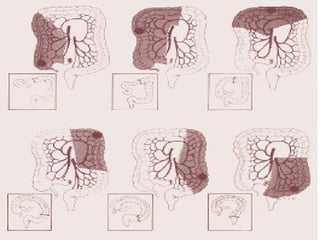

PRESENTACION POR REGIONES

 Ca. Colon ascendente 33%.

 Ca. Colon transverso 17%.

 Ca con descendente y sigmoides 36.4%.

 Ca recto15.7%.

CANCER DE COLONY RECTO FORMAS DE PRESENTACION  Ca. con esporádico 70 – 80%.  Ca. colon familiar 10 – 20 %.  Ca colon Polipoideo 1%.  Ca. Colon no polipodeio 5%. PRESENTACION POR REGIONES  Ca. Colon ascendente 33%.  Ca. Colon transverso 17%.  Ca con descendente y sigmoides 36.4%.  Ca recto15.7%.